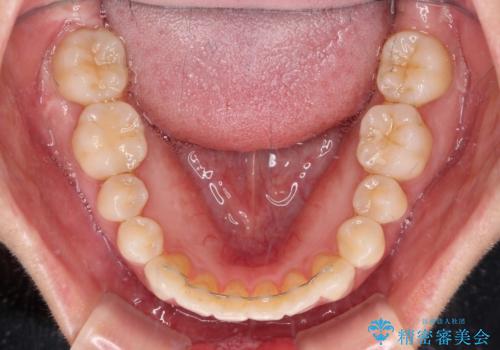

捻れた前歯をできるだけ短期間で 表側のワイヤー矯正

- 上下前歯のねじれを気にして来院された患者様です。

ワイヤー矯正でもマウスピース矯正でも対応可能でしたが、マウスピース矯正の自己管理が面倒であること、上顎前歯の捻転が著しいことから、ワイヤー矯正での治療を希望されました。

日々前歯の捻れが解消されていくので、歯の動きを楽しみながら矯正治療を進めることができました。